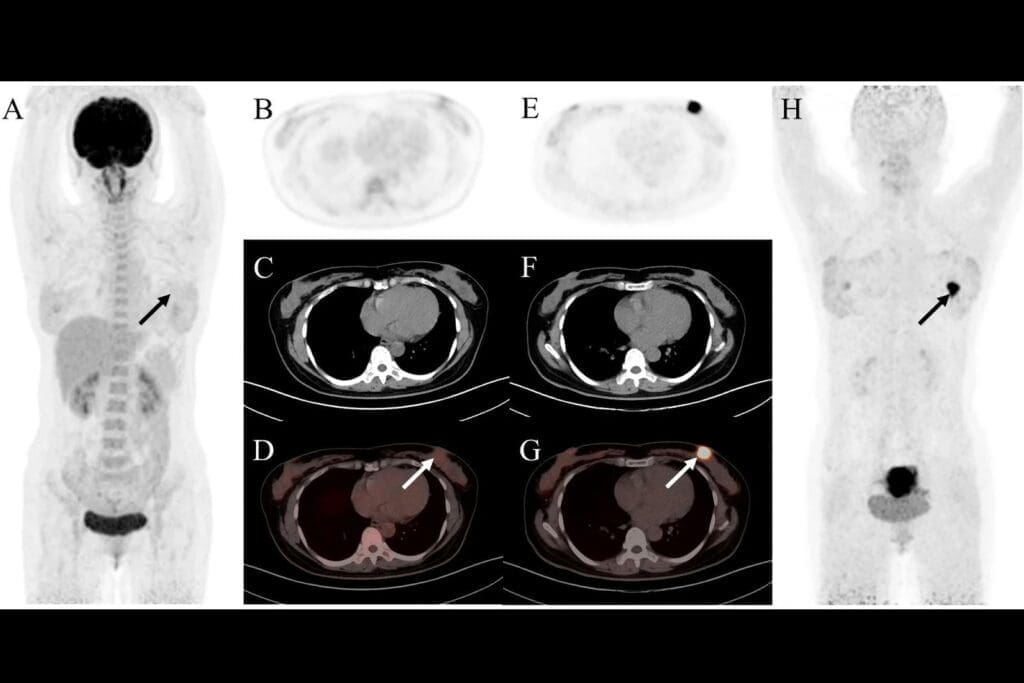

Detection of Urinary Tract Tumors

CT urograms are great at finding tumors in the urinary tract. They show us the kidneys, ureters, and bladder in detail. This helps spot tumors early, which is important for treatment.

These tests help us find and check tumors for cancer. The clear images from the CT scan help us decide how to treat them.

Acute Pyelonephritis

Acute pyelonephritis is an infection in the kidney, usually from bacteria. On CT urograms, it shows as renal enlargement with patchy or striated nephrograms. You might also see perinephric stranding, which means inflammation spreading beyond the kidney.

Renal and Perirenal Abscesses

Renal and perirenal abscesses are pus collections in or around the kidney, caused by infections. On CT urograms, they look like low-attenuation masses with rim enhancement. Perirenal abscesses can push against or compress nearby structures.